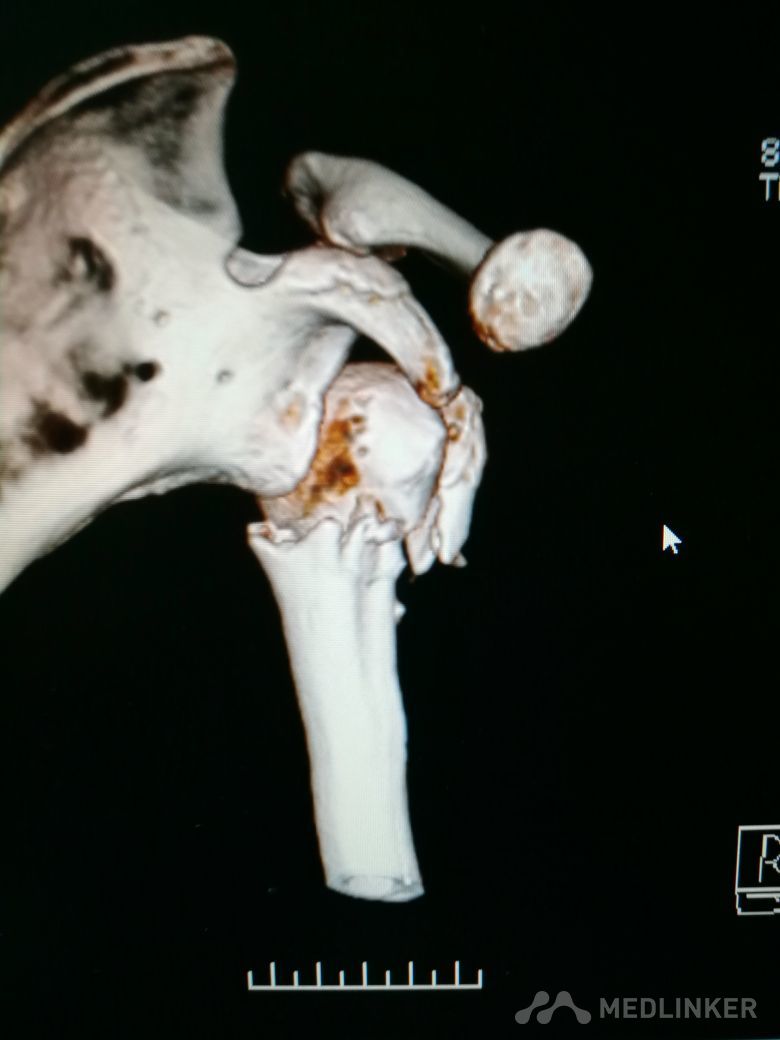

肱骨近端骨折 Neer IV型

患者,女性,55岁,因外伤致左肩疼痛六小时入院,既往无其他慢性病史

查体 右肩肿胀,畸形,活动受限,压痛,皮下淤血,右桡动脉搏动存在

完善相关检查,在腰麻下行右肱骨近端骨折切开复位内固定术

肱骨近端骨折占到肱骨骨折的45%,肱骨近端锁定钢板具有低切迹、高弹性、生物力学性能优良等特点,可以起到角度稳定控制旋转的作用。但是对于严重粉碎性肱骨近端骨折而言,单纯的肱骨近端锁定钢板不一定能够提供稳定的固定,手术之后仍有可能出现内翻塌陷、前后成角、螺钉切出、骨折畸形愈合、骨折不愈合等并发症。